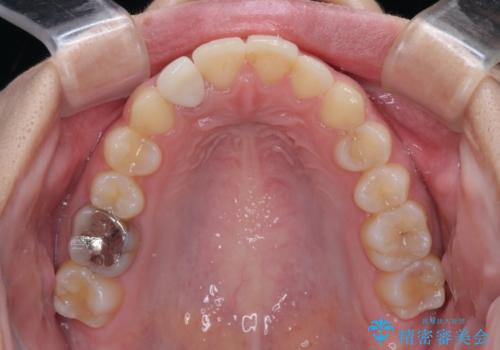

- 前歯の歯並びと不自然な色をした前歯のクラウンを気にして来院された患者様です。

上下前歯の歯列不正はインビザラインにより歯列を整え、その後に、前歯をオーダーメイドタイプのオールセラミッククラウンにて補綴治療することとしました。

前歯のデコボコを一番気にしていらっしゃいましたが、矯正治療により下顎前歯が隠れるほどのディープバイトも一緒に改善され、奥歯に負担のかかりにくい咬み合わせとなりました。